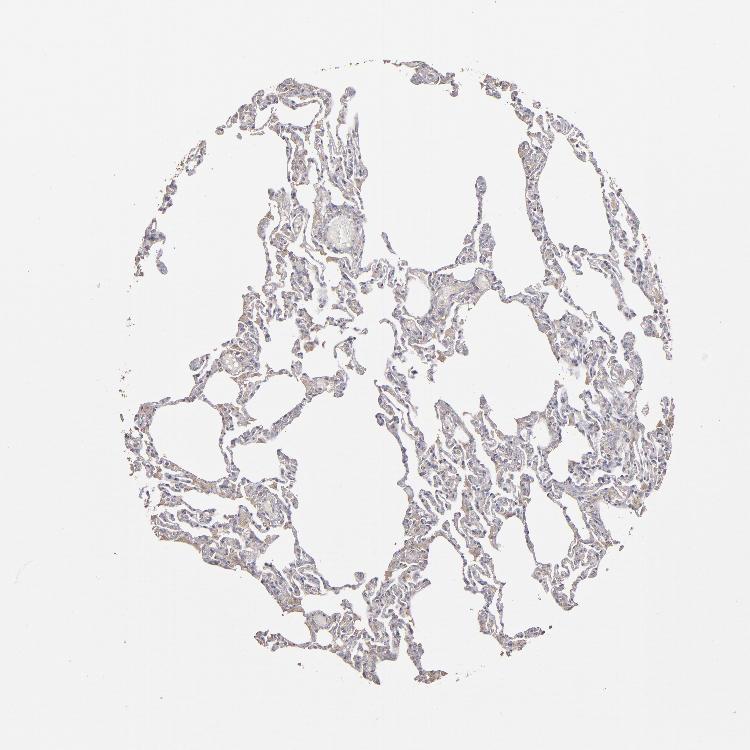

LUNG - Antibody stainingi

Antibody staining in the annotated cell types in the current human tissue is reported as not detected, low, medium, or high, based on conventional immunohistochemistry profiling in selected tissues. This score is based on the combination of the staining intensity and fraction of stained cells.

Each image is clickable and will lead to virtual microscopy that enables deeper exploration of all samples and also displays staining intensity scores, fraction scores and subcellular localization as well as patient and tissue information for each sample.

Antibody HPA001869Antibody HPA023882

Alveolar cells Not detectedMedium

Macrophages LowMedium